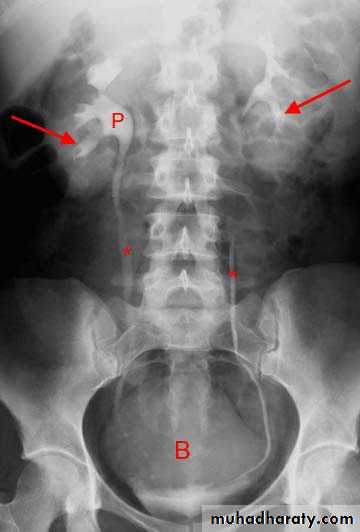

A. First a plain x-ray of the abdomen is taken before the injection of the contrast media, also known as A KUB (kidney, Ureter and Bladder). Calcification & stones may be obscured & missed by contrast media if plain film not takenfirst .

B. Films taken after injection of contrast’ medium:

A series of x-ray films are taken after injection of the contrast.

Each film is taken at a time interval determined by the radiologist who is supervising the procedure.

1.Nephrogram phase (Immediately after injection of contrast) .

2. Pyelogram Phase(l-5 minutes after injection of contrast) .